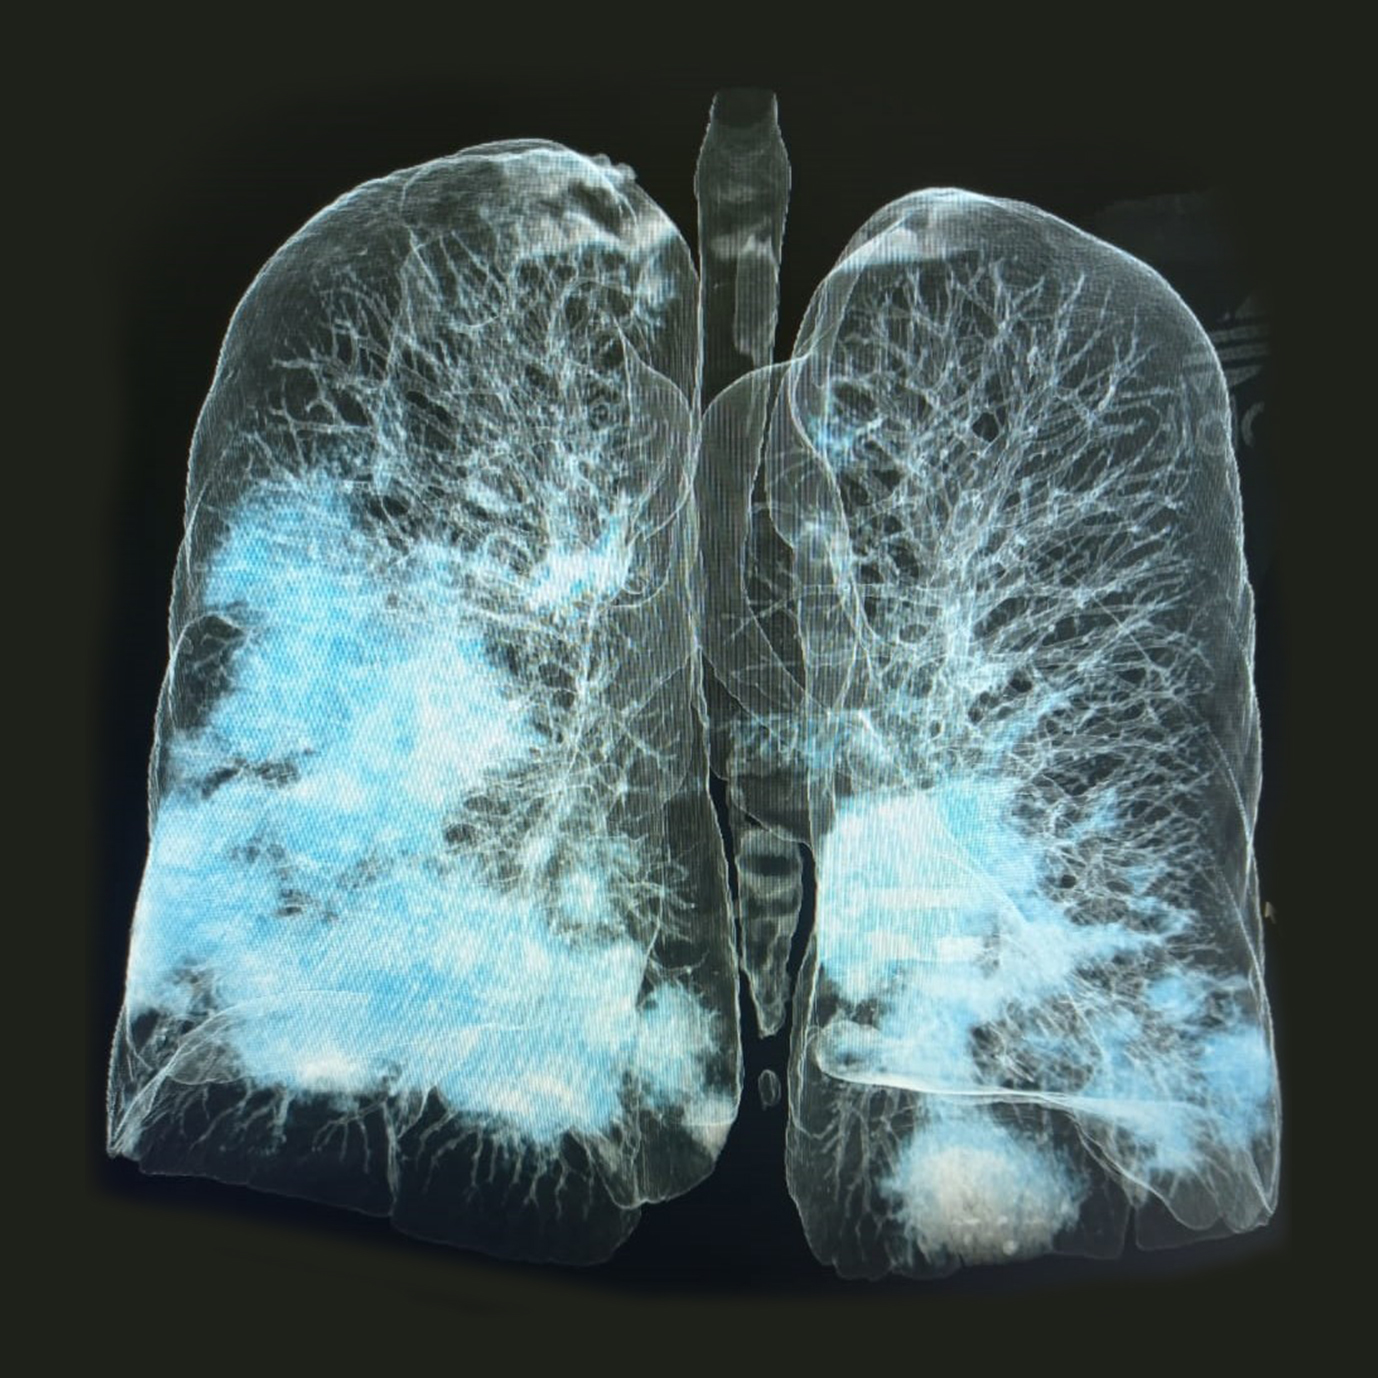

Ejemplos de estudios realizados en nuestra clínica.

con precisión avanzada para un diagnóstico confiable